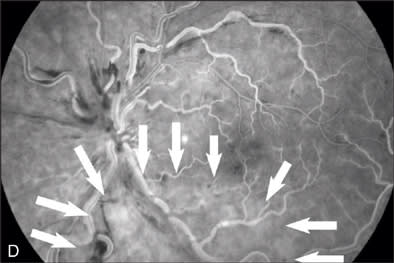

At our initial examination in August 2008, corrected visual acuity was 20/30 in the right eye and 20/50 in the left, with normal ocular pressure in both eyes. There were no rubeosis irides in either eye. Fundus examination appeared normal in the right eye while the left eye revealed a typical nonischemic CRVO (Figure 1A). Fluorescein angiography of the left eye (Figure 1B to 1E) showed generalized dilated, tortuous retinal veins, intraretinal hemorrhages, peripheral retinal non-perfusion areas, and microvascular leakage at the macula (Figure 1E, arrow). Despite the peripheral retinal ischemia, the macula itself was not ischemic at the first visit, as evidenced by the early phase FA showing 2 cilioretinal arteries supplying the fovea (Figure 1C, arrow). Spectral domain OCT (OPKO-OTI, Miami, FL.) confirmed the diagnosis of cystoid macular edema (CME). The patient got intravitreal bevacizumab (Avastin) injection (1.25 mg/0.05 mL) at the first visit.

At the 5-month follow-up visit in February 2009, corrected visual acuity remained 20/20 in the left eye, with normal ocular pressure in both eyes. There were no rubeosis irides in either eye. Fundus examination appeared normal in the right eye with improvement in the appearance of the retinal vasculature in the left (Figure 2A). Fluorescein angiography of the left eye (Figure 2B to 2E) showed resolution of the CRVO characteristics (dilated, tortuous retinal veins, intraretinal hemorrhages, peripheral retinal non-perfusion areas) with no microvascular leakage at the macula. Spectral OCT confirmed no cystoid macular edema (Figure 2E).

Figure 1F demonstrates the changes of oximetry between the 2 visits. The arterial oximetry changed from blue to red (red arrow), the venous oximetry changed from green to blue (yellow arrow). The non-perfusion area in the Figure 1F (appeared in blue) disappeared as shown in the follow-up visit report (Figure 2F), this was well correlated with the changes in the FA images in Figures 1D and 2D. The change to the nerve fiber layer infarction area was also observed on the oximetry, where it primarily appeared in white (Figure 1F, black arrow) then it disappeared in the follow-up visit report (Figure 2F), this change was also well correlated with the change between the red-free images (Figure 1B, arrow outlined, and Figure 2B).